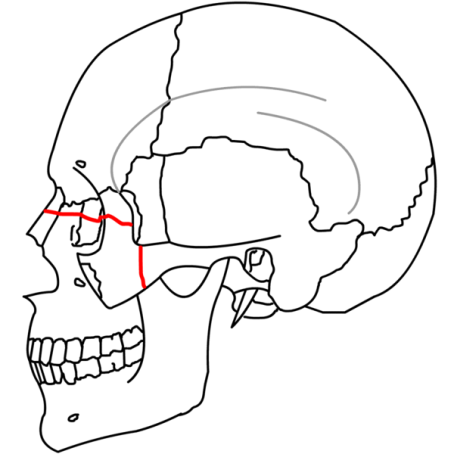

| Lefort II - Pyramidal shaped fracture - the fracture goes thru the nasofrontal suture, thru the lacrimal bones and down thru the infraorbital rims | |

![]() |